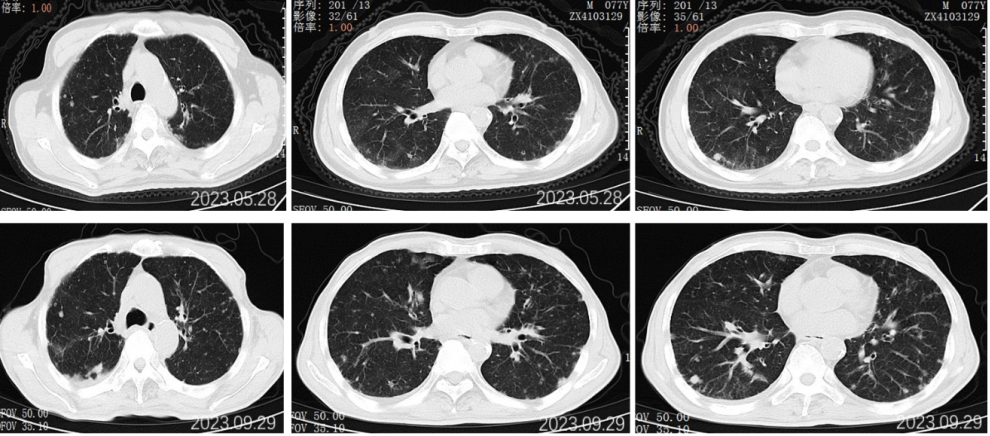

2022.11.25胸部CT平扫:对比2022-09-27影像:1.新见两肺多发间质性肺炎样改变,感染考虑,VP-RADS 2类;2.两肺多发小结节、类结节影,部分较前略缩小,转移性考虑;3.左侧第5后肋骨质破坏,相仿。

2023.5.28胸部CT平扫:对比2022-11-25片:1.两肺散在多发炎症,较前相仿,VP-RADS 2类;2.两肺多发小结节、类结节影,转移瘤考虑,较前相仿;3.左侧第5后肋骨质异常,相仿。男性乳腺发育。

2023.09.29胸部CT平扫:对比2023-05-28片:1.两肺多发小结节、类结节影,较前增多增大,转移瘤考虑。2.两肺散在多发炎症,部分较前吸收;3.左侧第5后肋骨质异常,相仿;4.右侧胸腔少量积液。男性乳腺发育。